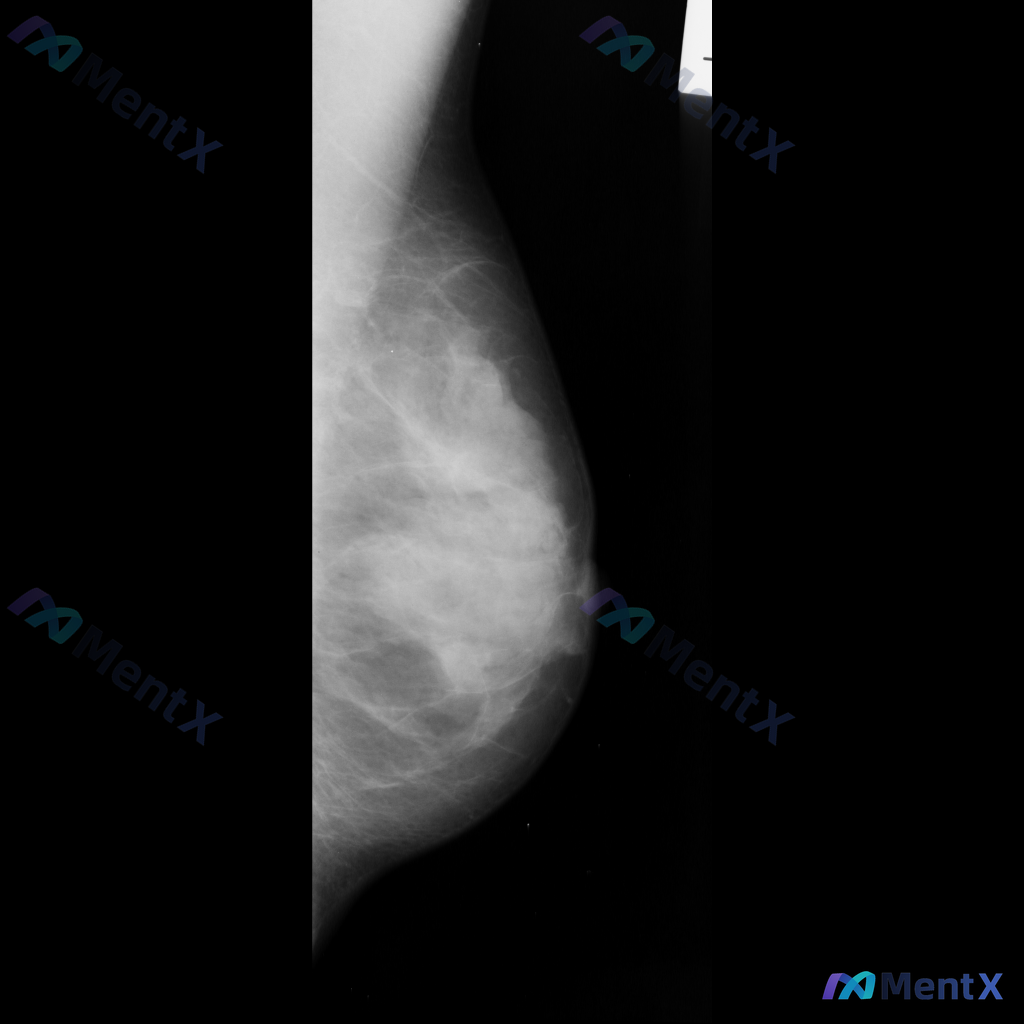

整理到一张乳腺钼靶影像的读片讨论资料: 影像显示右乳腺局部区域存在一不规则高密度肿块,伴有毛刺状边缘及局灶性结构扭曲。 想先跟大家讨论一下:单看这组特征,你首先会往哪个方向考虑?后续又会建议如何处理?